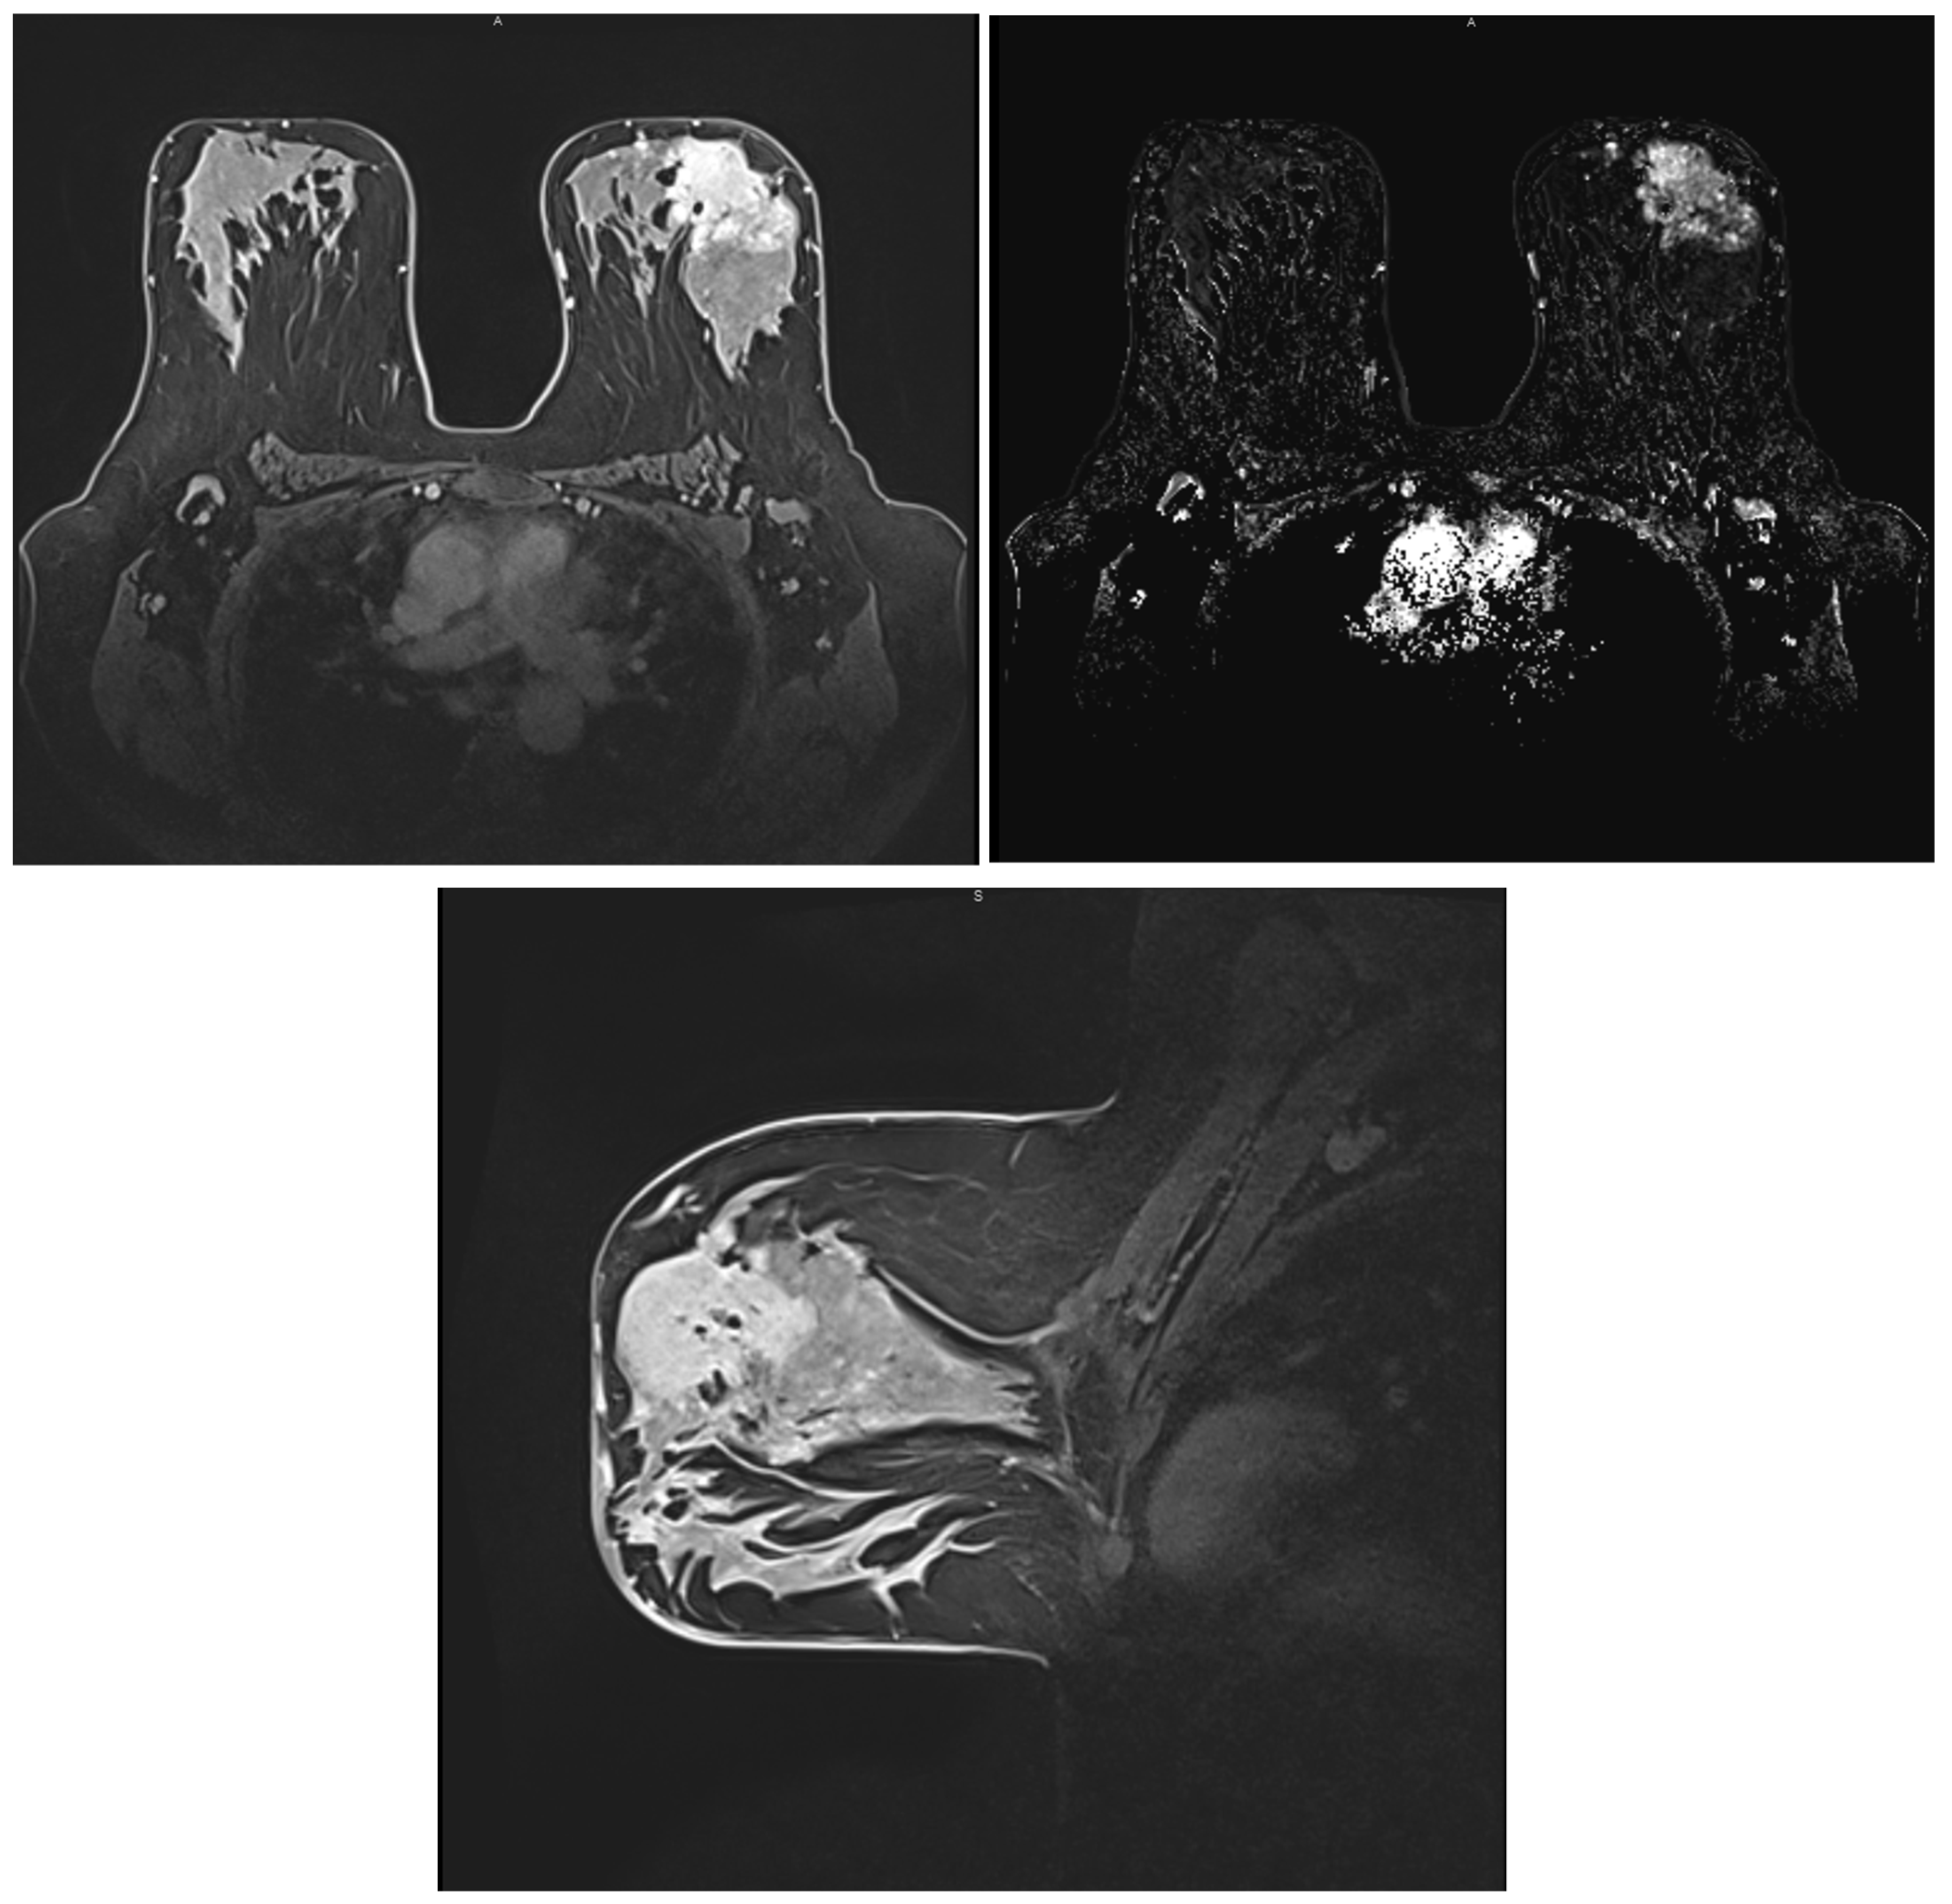

2.4. Magnetic Resonance Imaging (MRI)

3.7. Correlations between Molecular Subtypes of BC and Their Features on MRI

- Szep, M.; Pintican, R.; Boca, B.; Perja, A.; Duma, M.; Feier, D.; Fetica, B.; Eniu, D.; Dudea, S.M.; Chiorean, A. Multiparametric MRI Features of Breast Cancer Molecular Subtypes. Medicina 2022, 58, 1716. [Google Scholar] [CrossRef] [PubMed]

- Öztürk, V.S.; Polat, Y.D.; Soyder, A.; Tanyeri, A.; Karaman, C.Z.; Taşkın, F. The Relationship Between MRI Findings and Molecular Subtypes in Women With Breast Cancer. Curr. Probl. Diagn. Radiol. 2020, 49, 417–421. [Google Scholar] [CrossRef]

- Ab Mumin, N.; Ramli Hamid, M.T.; Wong, J.H.D.; Rahmat, K.; Ng, K.H. Magnetic Resonance Imaging Phenotypes of Breast Cancer Molecular Subtypes: A Systematic Review. Acad. Radiol. 2022, 29, S89–S106. [Google Scholar] [CrossRef] [PubMed]